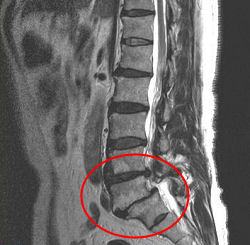

すべり症の患者さんで、MRIの写真を持参されたので考察してみました。

腰の骨すべり症のMRI

腰の骨すべり症 25%

腰の骨5番が、25%(1/4)前方にすべっているのが見られます。

その位置で脊髄神経が折れ曲がっているのが分かります。

また腰の骨3番4番にも、ヘルニアが見られています。